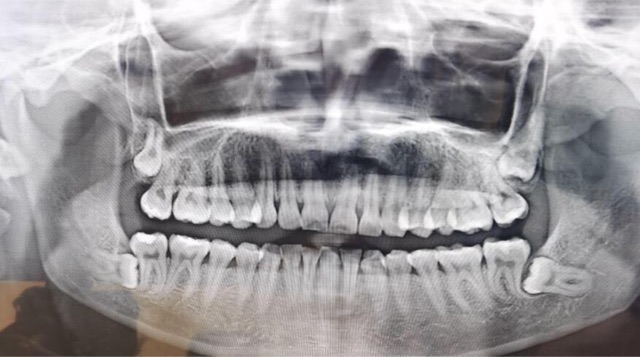

智齿,也称为第三磨牙,是人类的额外一对臼齿,通常在16岁至25岁之间开始出现。它们是人类进化的痕迹,起源于远古时期我们祖先的食物选择的变化。然而,由于智齿的生长常伴随着问题和不适,许多人需要通过拔牙来解决这些问题。智齿的问题主要源于其冠部的生长问题。由于人类的口腔逐渐缩小,智齿往往没有足够的空间来正常生长和发育。【周边网】

智齿可能不在正确的位置上,可能向前倾斜、向后倾斜或垂直倒置。这些错位可能对邻近的牙齿造成压力和移位,导致不适和疼痛。

智齿可能仅部分冒出牙龈表面,造成牙龈肿胀和不适。为了解决这些问题,许多人选择拔除智齿。根据情况的严重程度,医生会决定是否需要拔除智齿。拔除智齿通常是在局部麻醉下进行,医生会在口腔内提供适当的舒适度。